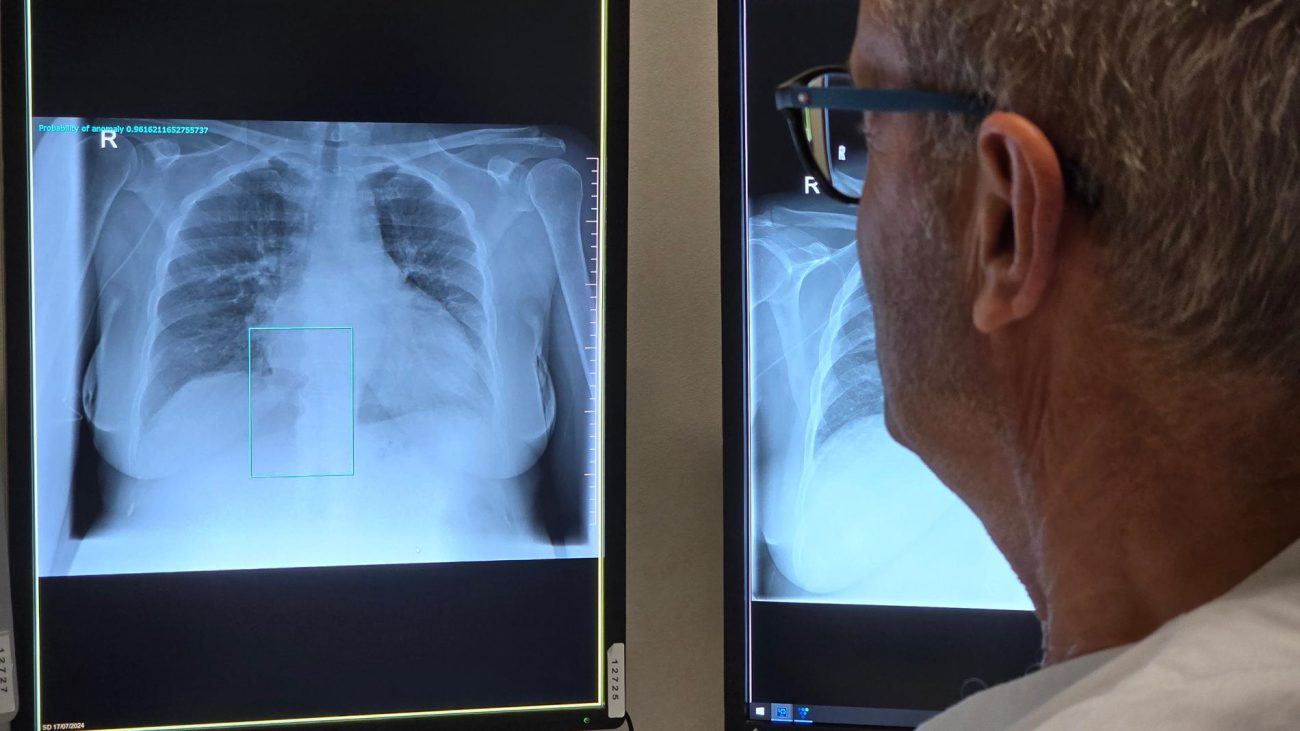

La detección temprana, mediante tomografía computarizada de baja dosis (LDCT), puede reducir hasta 24 % la mortalidad por cáncer de pulmón en personas de alto riesgo, de acuerdo con el estudio Nelson, realizado en Países Bajos y Bélgica.

El ensayo, publicado en la revista estadounidense The New England Journal of Medicine, mostró que el tamizaje con LDCT detecta el 59 % de los casos en etapas iniciales, frente a 14 % en el grupo sin tamizaje, y reduce la mortalidad en hombres en 24 % y en mujeres en 33 %.

La incorporación de IA en el análisis de imágenes médicas permite identificar nódulos pulmonares de pocos milímetros, comparar patrones radiológicos con bases de datos globales y generar alertas automáticas sobre posibles anomalías, complementando la labor de los radiólogos, disminuyendo los falsos negativos y acelerando el diagnóstico, factores clave para iniciar tratamiento en etapas tempranas y mejorar la sobrevida.

Primer programa estatal con IA en México

En el marco del Día Mundial del Cáncer de Pulmón, la Secretaría de Salud del estado de Nuevo León (México) firmó un convenio con el Hospital Universitario ‘Dr. José Eleuterio González’ de la Universidad Autónoma de esa región (UANL) y la farmacéutica AstraZeneca para implementar el primer programa estatal de tamizaje con inteligencia artificial para cáncer de pulmón en México, según informó la dependencia.

El convenio firmado busca intervenir en etapas tempranas empleando algoritmos que procesan miles de imágenes y señalan automáticamente las zonas con irregularidades en los casos de cáncer de este tipo que, según Globocan, en 2022 representó la quinta causa de muerte por cáncer en México, con cerca de 9.000 nuevos casos y más de 7.000 decesos anuales.

En el Hospital Universitario de la UANL ya se han realizado más de 17.500 escaneos con esta tecnología, mostrando alta precisión en la detección de lesiones. Ahora, en la nueva fase del proyecto, busca extender el sistema a hospitales públicos de segundo nivel, iniciando con el Hospital Metropolitano, para consolidar un circuito estatal de detección temprana.